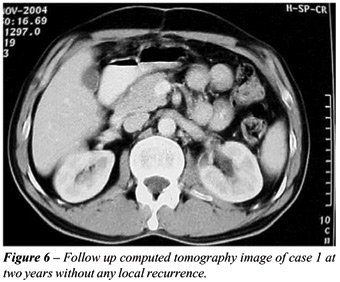

Both patients were discharged after 72 hours postoperatively without any complication. Patients were kept on a three monthly follow-up. Computed tomography images were repeated at 6 month intervals for two years. At present, both patients are completely asymptomatic, free of local recurrence (Figure-6) or distant metastases.